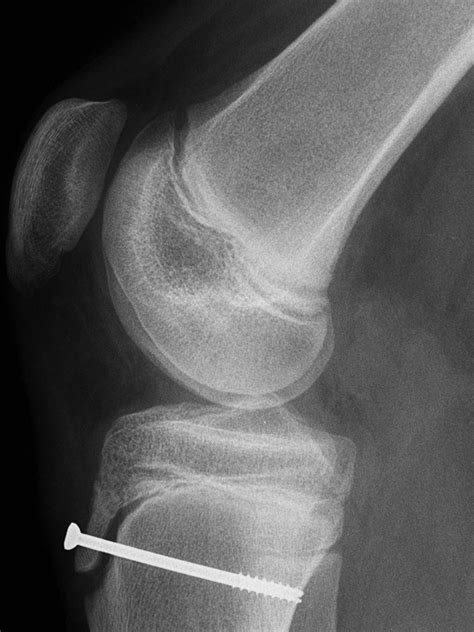

The surgical procedure is typically performed under general or regional anesthesia. The surgeon makes a small incision over the tibial tubercle, the area where the pain is localized. Once the area is exposed, the surgeon carefully identifies the ossicle or the prominent bony protrusion. Using specialized instruments, they remove the bony fragment while being extremely cautious not to damage the attachment point of the patellar tendon itself, as this is critical for knee extension.

Pre-Op Clinical assessment and MRI/X-ray confirmation of the ossicle.

Procedure Surgical excision of the ossicle and soft tissue debridement.